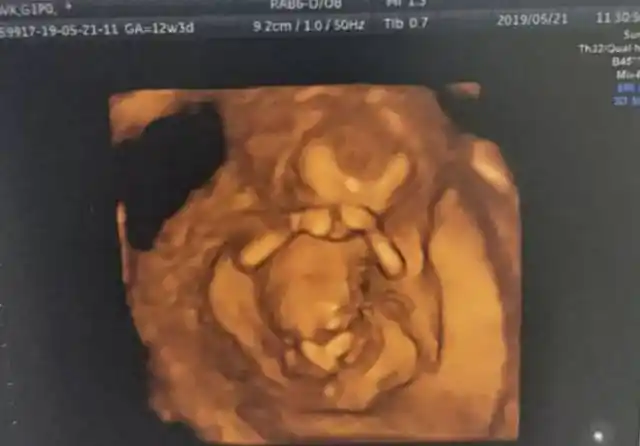

胎儿从卵泡到性别形成17张图片清晰诠释男宝女宝看得很清楚

怀孕十二周,生男生女这样看._手机搜狐网

怀孕12周,b超影像记录下胎动真相的珍贵时刻,好神奇的一幕!